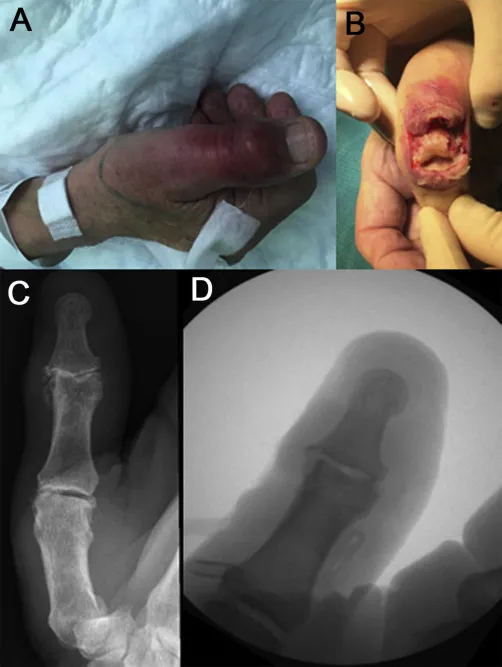

Can bone infections recur after treatment?

With proper surgical debridement, appropriate antibiotic therapy, and complete infection eradication, recurrence rates are low. Long-term follow-up is essential to monitor for any signs of recurring infection.

Is the treatment painful?

Pain is well-managed with appropriate medications throughout treatment. Most patients experience manageable discomfort during the adjustment phases, which gradually improves as healing progresses.